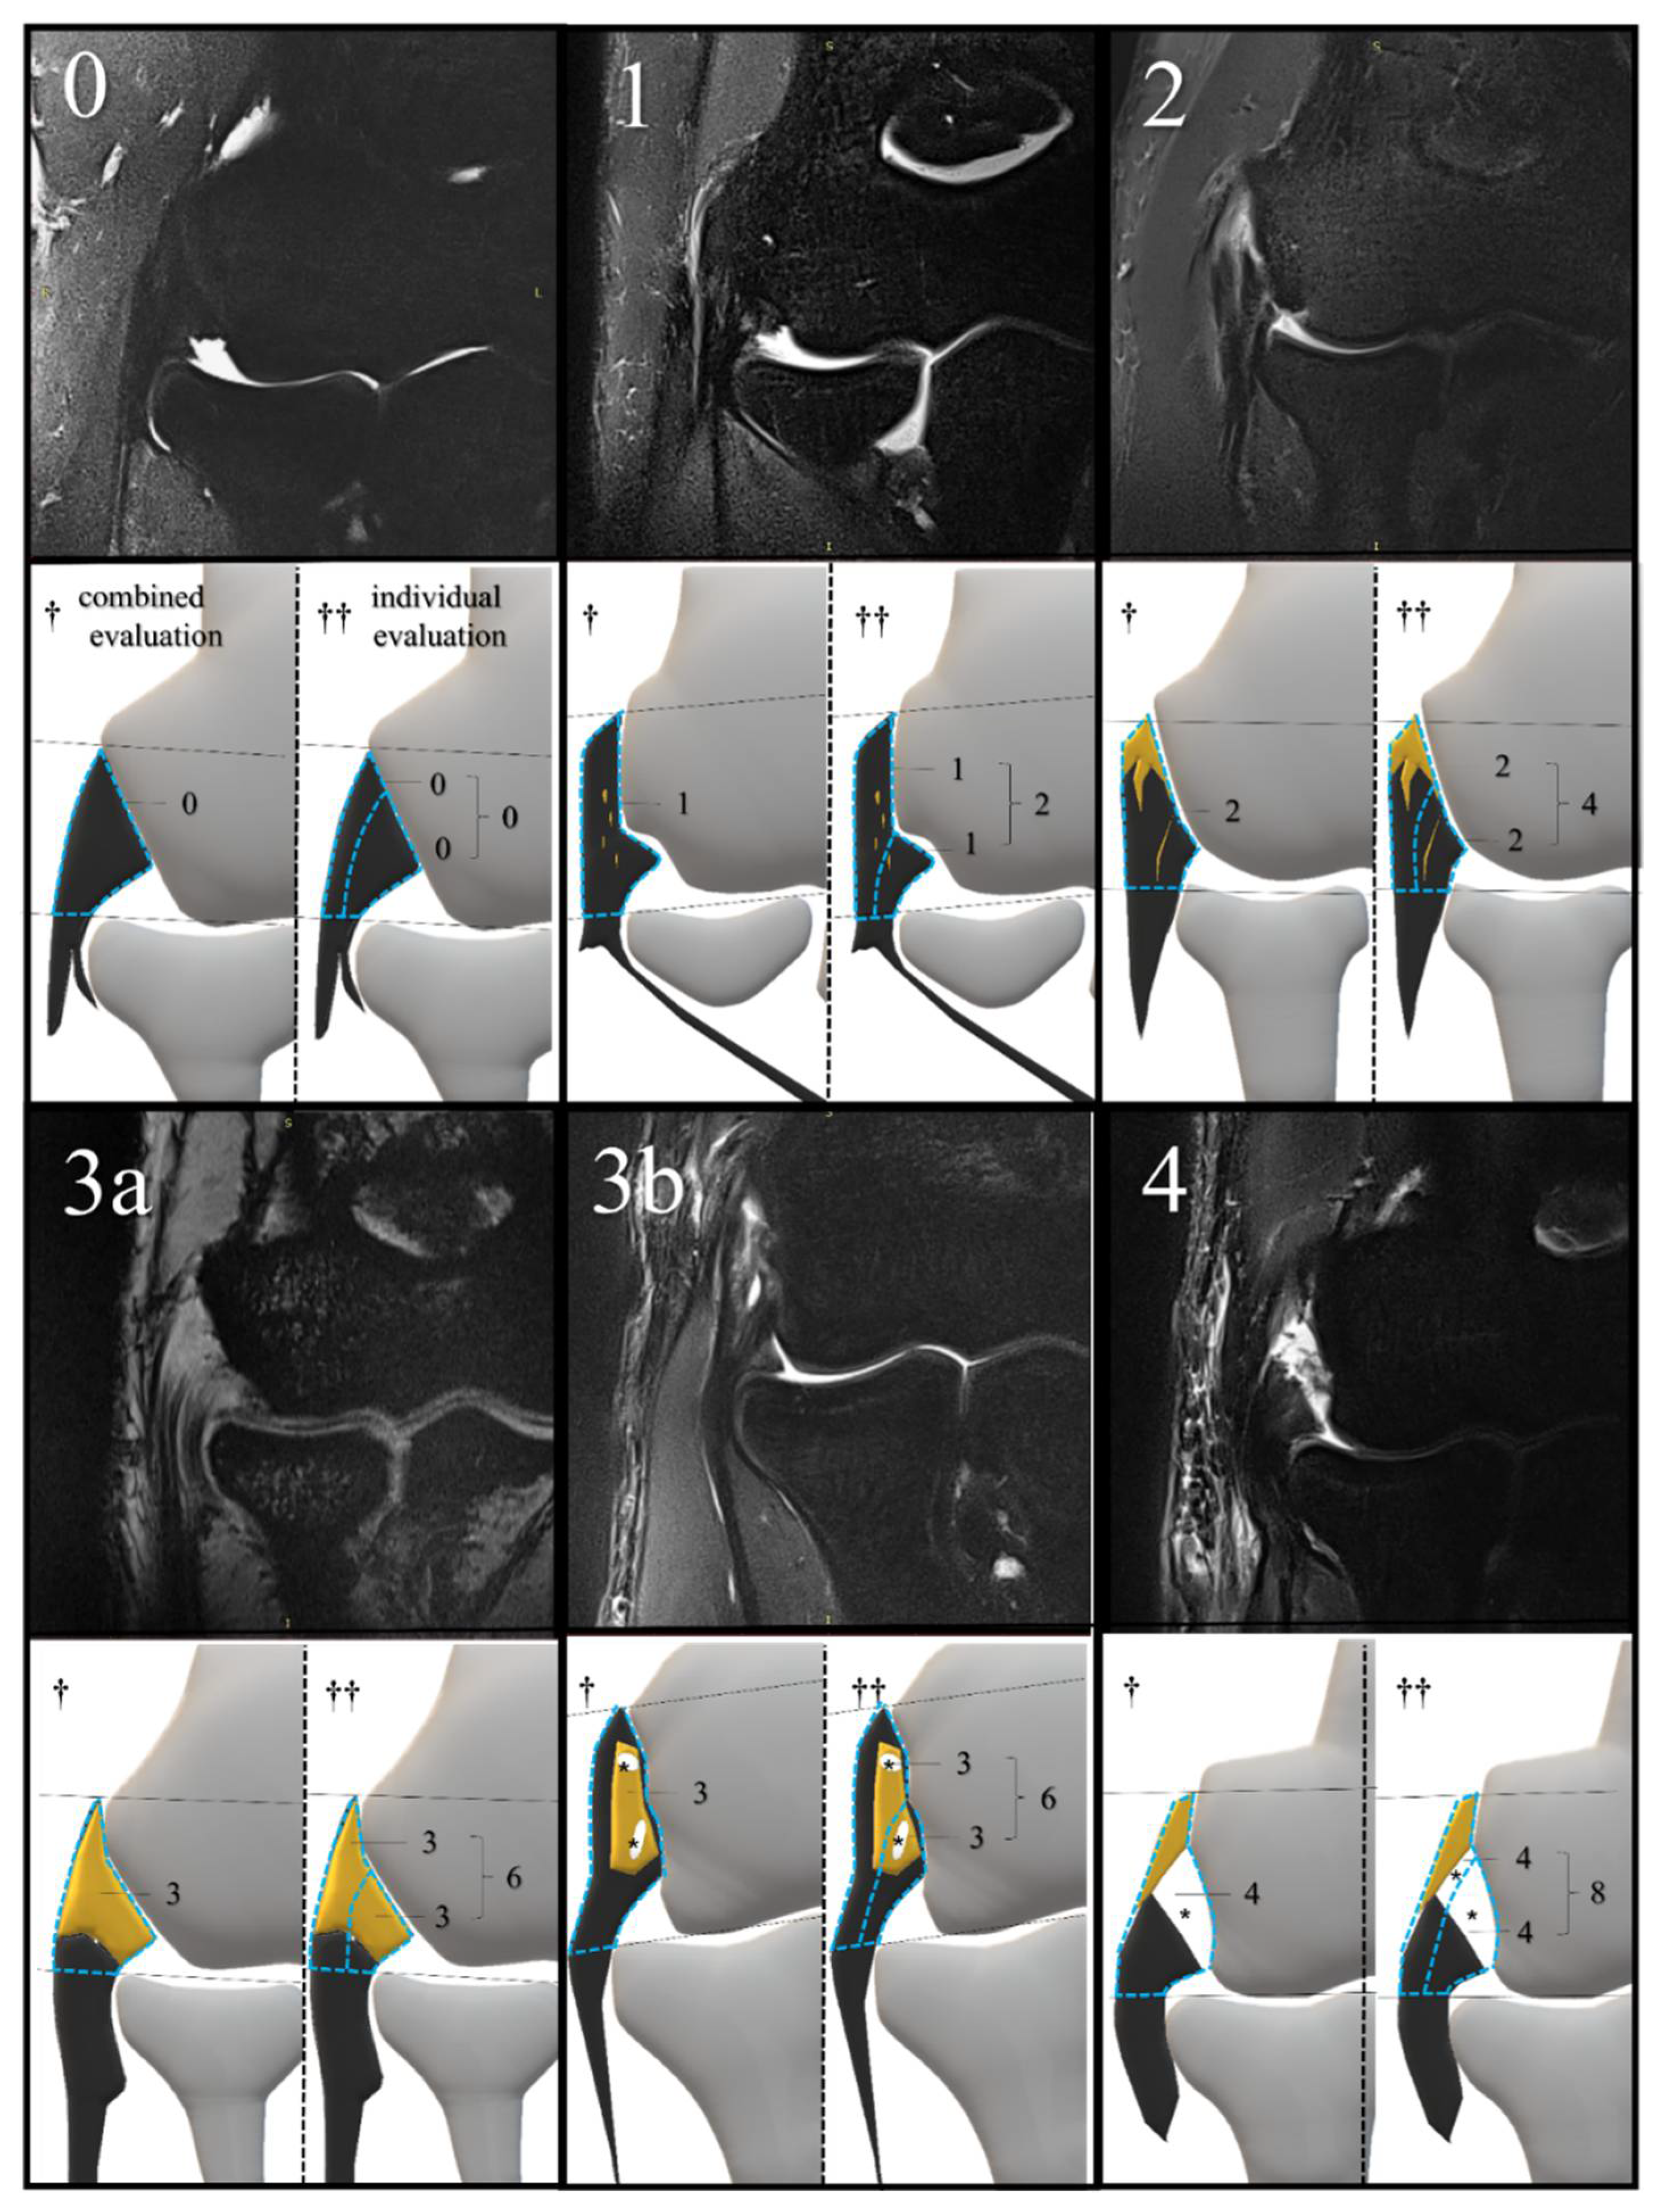

With reference to the previous literature [30,31], we created an MRI scoring scale which evaluated the strength and extent of signal changes within a coronal section on a scale of 0 to 4. The region of interest for our MRI scoring was the CET and the LCL between the articular surface of the radial head and lateral epicondyle of the humerus. Using this MRI scoring, we performed two patterns of MRI evaluation. The combined evaluation method evaluated the CET and the LCL together on a scale of 0–4. In contrast, the individual evaluation method evaluated the CET and the LCL individually on a scale of 0–4 and subsequently added the individual scores for a total score of 0–8 (Figure 4).

Figure 4.

MRI examples of each score and its corresponding schema. The scoring criteria are as follows: (0) (normal), dark, linear low-signal structure without changes in signal intensity; (1) (mild degeneration), thickening or mild signal change below the signal intensity of the muscle; (2) (localized degeneration), high signal change above the signal intensity of the muscle, localized below 50% of the evaluation range; (3a) (extensive degeneration), high signal change above the signal intensity of the muscle, beyond 50% of the evaluation range; (3b) (partial tear), high signal change equivalent to joint fluid, within 75% of the tendon or ligament width; (4) (extensive tear), high signal change equivalent to joint fluid, more than 75% of the tendon or ligament’s width. The yellow area indicates degeneration; * tear; MRI, magnetic resonance imaging. The blue dotted line surrounds the region of interest for MRI scoring in each evaluation method. Black lines are auxiliary lines to determine the evaluation area, which runs parallel to the articular surface of the radial head. † combined evaluation; †† individual evaluation; yellow area, degeneration.